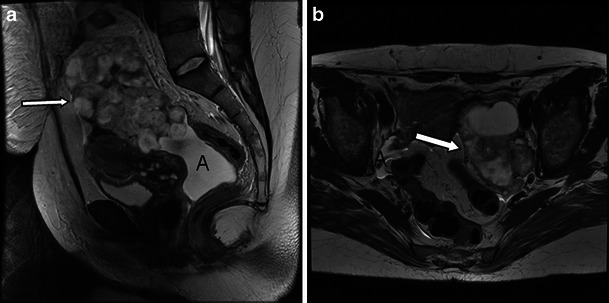

The diagnosis of malignant struma ovarii is usually based on histological features of the resected ovary, as no specific imaging features are available to detect malignant struma. However, as malignant struma ovarii are teratomas, the following criteria apply to detect malignancy: CT and MR imaging findings of malignant transformation of ovarian teratoma include invasive growth of large, irregularly marginated soft-tissue components through the tumour wall or irregular soft-tissue components within the tumour [37] (Figs. 8 and 9). In view of the ascites frequently present in benign struma, distinguishing benign from malignant struma is difficult in the absence of extracapsular extension (Fig. 8). The potential future role of diffusion-weighted imaging to distinguish benign from malignant struma remains to be investigated in a large multicentre trial. In our limited experience ADC values in malignant struma overlapped with those of benign struma. However, in this limited cohort of only two cases, the tumour burden in the struma on histopathology was limited.

Fig. 8.

Three-tesla T2 high-resolution images of a benign and malignant struma ovarii for comparison. a Sagittal image showing the large mixed solid and cystic malignant struma (arrow). b Axial plane image through a benign struma shows an equally complex large lesion (arrow). a, b Ascites is present in both the benign and the malignant case (A)